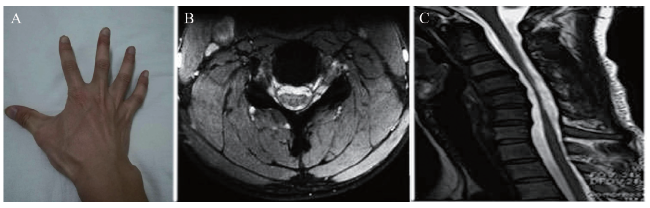

例 1,患者男,16岁,高中学生,山东济宁人,现居地为山东省济宁市,因“右手和右侧上肢无力1年,持物困难”于2011年9月15日入我院。患者无烟酒等不良嗜好。无传染病史和手术外伤史。父母与兄弟身体状况良好,家族成员中未发现遗传病及传染病。体格检查:神志清晰,语言流利,颅神经检查正常,锥体束征阴性。右手骨间肌、大小鱼际肌、蚓状肌明显萎缩,双侧前臂尺侧肌肉明显萎缩,呈斜坡状,桡骨膜反射稍微降低(图1A)。双侧上肢肌力、肌张力和感觉正常。双侧肘关节、肩关节活动正常。双侧下肢肌力、肌张力和感觉正常,膝踝反射对称活跃,脊柱无畸形,无扣压痛。实验室检查:肌酸磷酸激酶(CPK)、乳酸脱氢酶、血肌酸正常,脑电图、脑脊液常规正常。颈椎过屈位MRI显示颈3 ~ 胸1椎体水平硬膜外腔增宽、硬脊膜增厚前移,横断面显示脊髓前后径变扁(图1B、C)。肌电图显示右侧正中神经和尺神经神经源性损害,神经传导速度大致正常。肌肉病理活组织检查(活检)报告显示肌纤维成角萎缩,提示神经源性肌损害。诊断为平山病。给予佩戴颈托、物理治疗以及口服维生素B治疗后于2011年10月23日出院。随访5年,患者病情稳定,预后良好。

图1 一例平山病患者右手外观与检查

A:右手肌肉萎缩;B:椎体横断面显示脊髓前后径变扁;C:颈3 ~ 胸1椎体水平硬膜外腔增宽